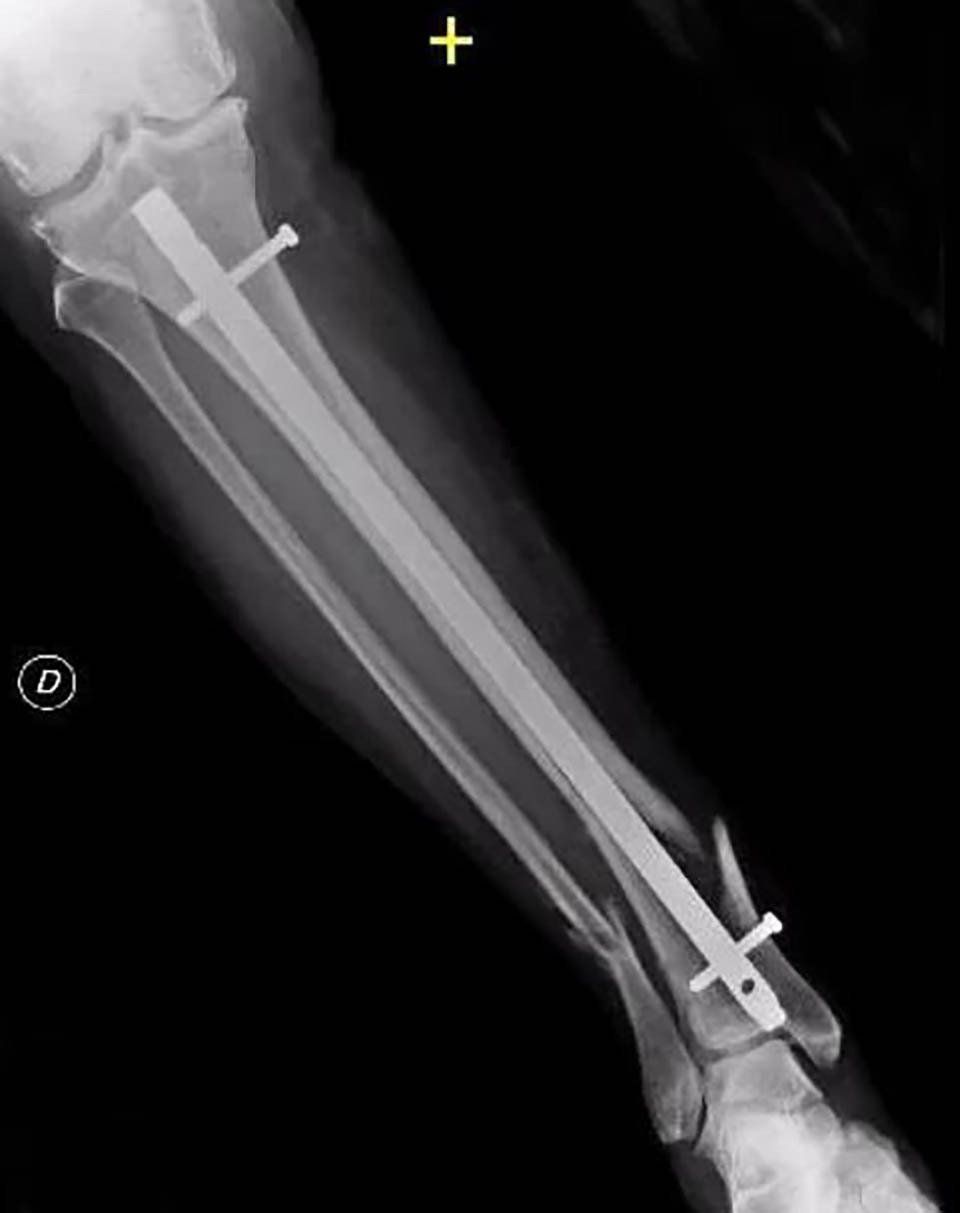

- Internal fixation: Orthopaedic surgeons use intramedullary nails, metal plates, and screws to stabilise pseudoarthrosis. Often, bone grafts are used to assist stability and promote healing.

- External fixation: Orthopaedic surgeons apply an external device to the affected limb using steel wires and pins. This method is preferred for pseudoarthrosis without sufficient stability, infected cases, or those with bone loss.